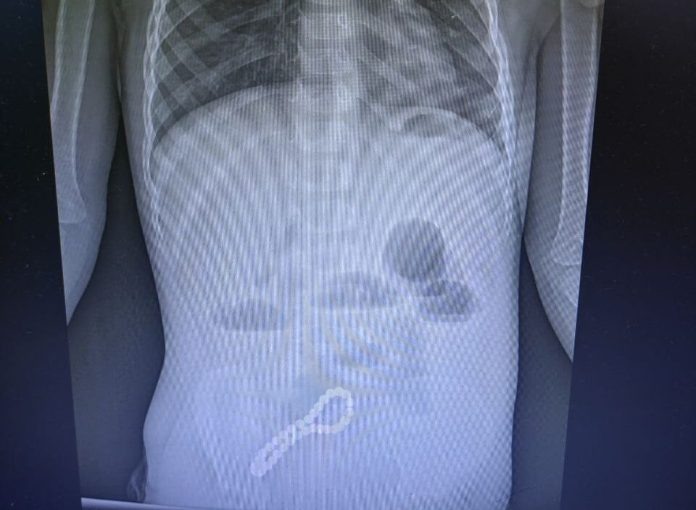

Врачи заподозрили проблему с кишечником, и рентгенография подтвердила их опасения. Несмотря на небольшой размер шариков, медики диагностировали инородное тело в кишечнике, которое необходимо было удалить.

Было принято решено провести операцию. Хирурги выполнили минилапаротомию — хирургическое вмешательство через разрез передней брюшной стенки. В ходе операции они обнаружили, что магниты, притянувшиеся друг к другу, соединили петли кишки, а в её стенке образовались отверстия. Врачи удалили все 30 магнитных бусин: 29 маленьких и одну большую. После операции ребёнок быстро восстановился, и его жизни и здоровью ничего не угрожает.